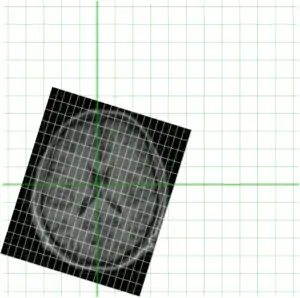

In order to get a better understanding of how mni_autoreg or indeed linear registration works, here is a simple example. Suppose we have an image of an individual and wish to align this with a model. These two images are shown below, the individuals image on the left (indiv.mnc) and model (model.mnc) on the right. Note that both of these files have different sampling and voxel sizes as illustrated by the white lines

Of course being a MINC file, both of these files represent a sampling of a world space (as defined by starts, steps and direction cosines -- use mincinfo to see this). In order to get an understanding of this, our two files are shown again below with their relative position in world space shown in green.